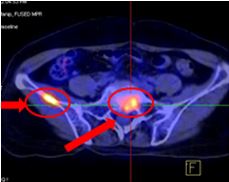

Tổn thương xương cánh chậu phải max SUV=5,34, Tổn thương S1,Max SUV=4,4 |

Trước điều trị: - Đau xương chậu nhiều - Tổn thương xương cánh chậu phải max SUV=5,34 - Tổn thương xương cùng S1, Max SUV=4,4 | Sau điều trị: - Không đau xương - Không còn tổn thương di căn xương